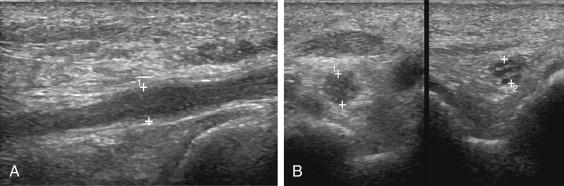

F igure 11-3, Partial-thickness tendon tear in different patients. A, Transverse view of the posterior tibial tendon (cursors) shows a distinct hypoechoic defect in the superficial aspect of the tendon consistent with a partial tear. B, Longitudinal view of the posterior tibial tendon (cursors) in another patient shows a distinct, linear, hypoechoic, longitudinally oriented partial tear in the central aspect of the tendon. Transverse gray-scale (C) and power Doppler (D) views of the posterior tibial tendon (cursors) show a central hypoechoic defect with increased vascularity.